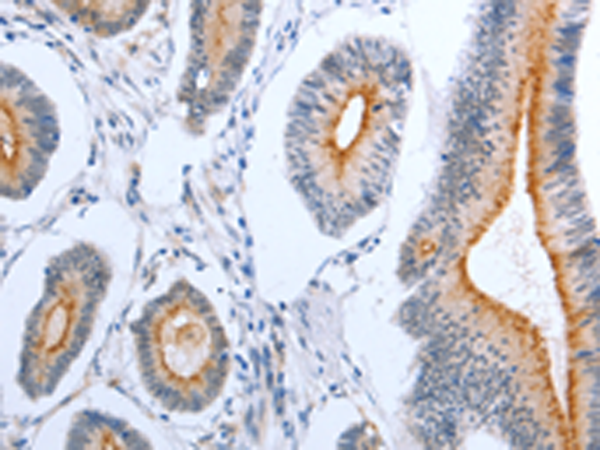

分类: 科研抗体货号: P07549别名: PGFL; PIGF; PLGF; PlGF-2; D12S1900; SHGC-10760应用: WB,IHC反应种属: Human